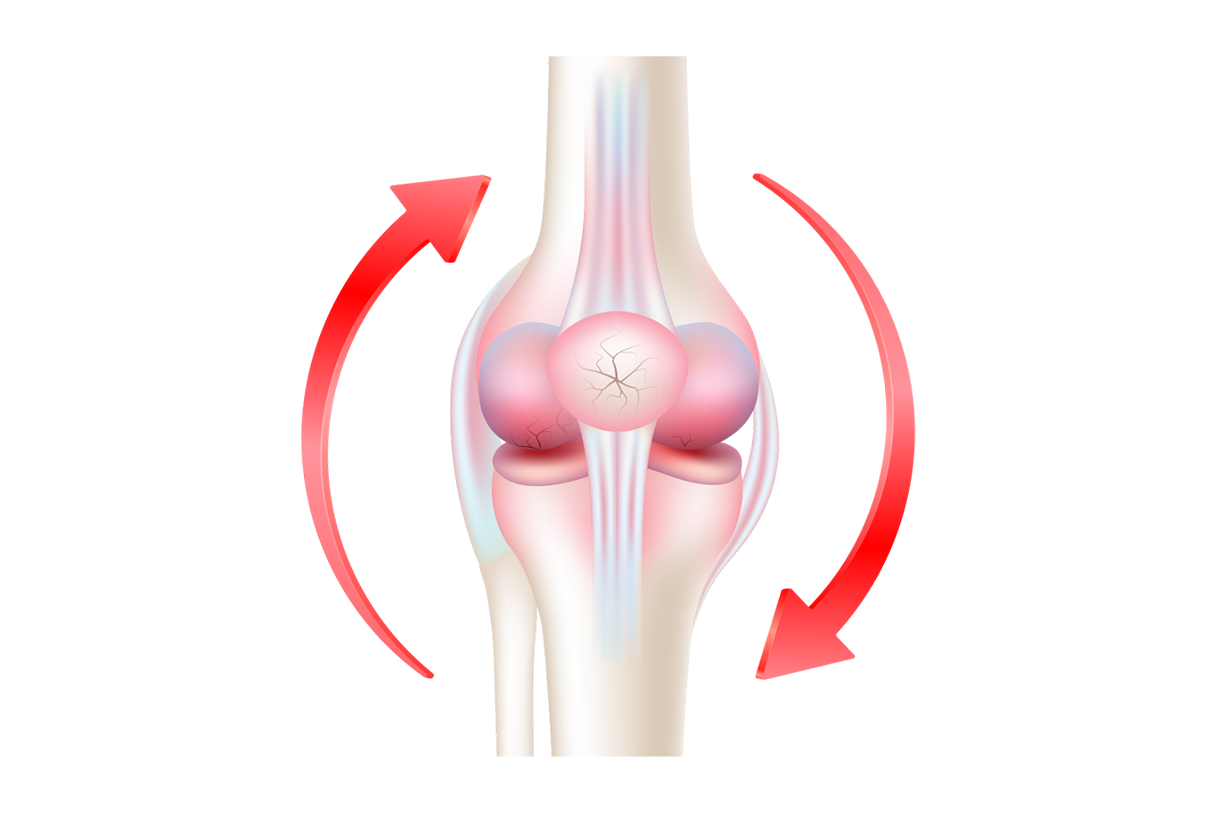

Wspiera odbudowę chrząstki stawowej i tkanek łącznych dzięki kolagenowi NatiCol®

Zmniejsza sztywność i bolesność stawów, poprawia komfort ruchu na co dzień